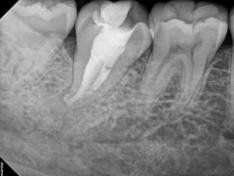

Root Canal Treatment

Every tooth has different numbers of roots and canal systems. With the help of magnification and high tech equipment, Dr. Jung can locate and treat the canals including MB2 on upper molars and MM on lower molars.